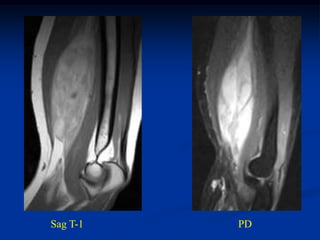

Case #251

11 year male with desmoid foot

Sagittal T-1 MRI

Axial T-1 MRI

Axial T-2 MRI